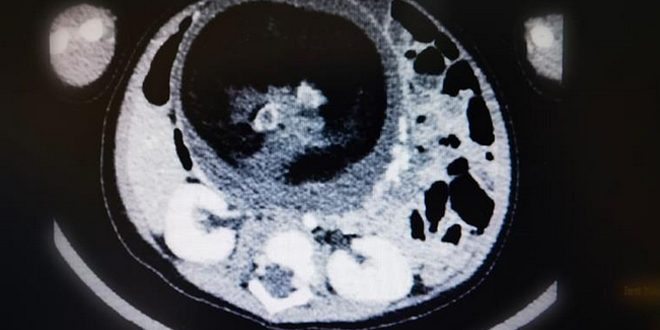

نجح قسم جراحة الأطفال بالمستشفى السلطاني في عمان بإجراء عملية جراحية نادرة لاستئصال جنين من داخل طفل يبلغ من العمر ثمانية أشهر وهي حالة نادرة الحدوث عالميا لكونها تتم في ظروف استثنائية.

يذكر أن هذه الظاهرة الطبية تعرف باسم (جنين داخل جنين) وتحدث بنسبة 1 من كل 500 ألف حالة ولادة حية على مستوى العالم.